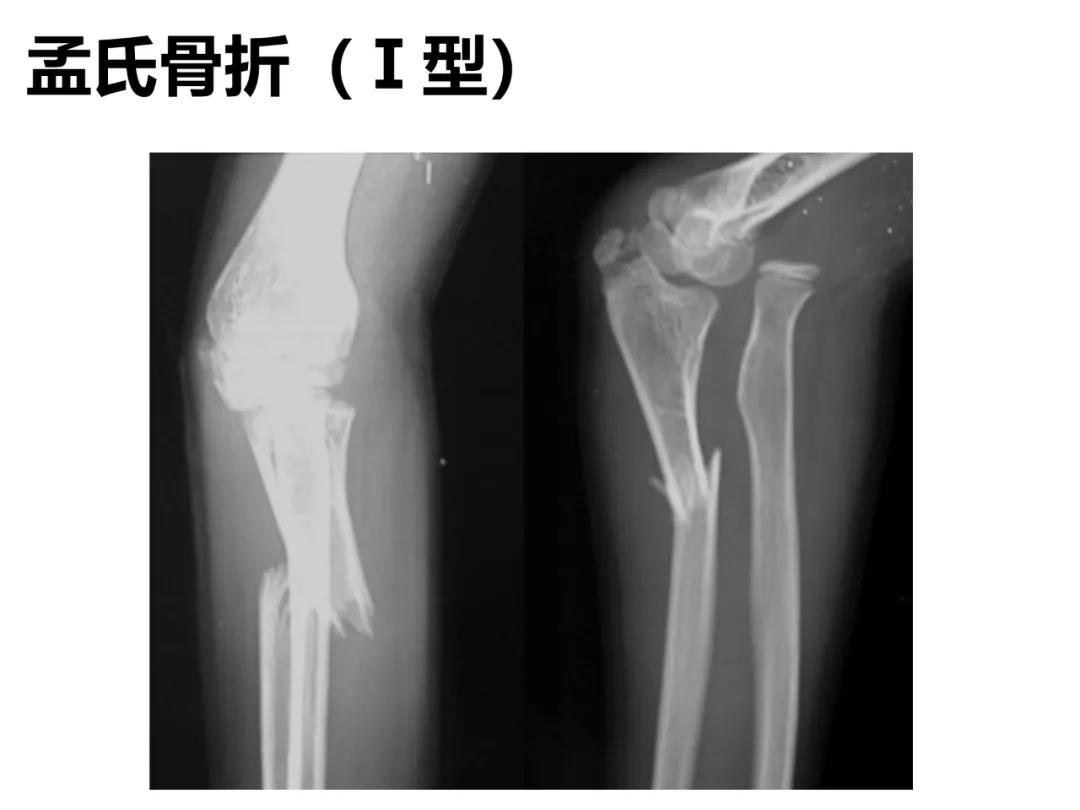

小儿骨科X线片汇总,临床读片宝典!